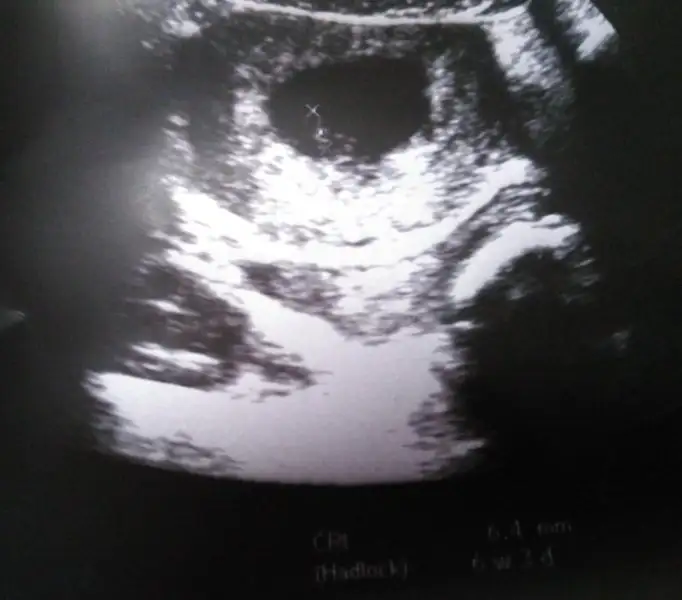

Sağol canm ya aynı seninki gibiymis sanırım o bebegn yanındaki yolk saç demnden beri ona bakıyorum bu ney diye cozemedm seninkide bnmkine benziyor dur atimTatlım attım hatta iki kere attım :))) B Biravucmutluluk

Doktor da yolk sac dedi küçük bir çıkıntı var solda o kalbiymiş :)Sağol canm ya aynı seninki gibiymis sanırım o bebegn yanındaki yolk saç demnden beri ona bakıyorum bu ney diye cozemedm seninkide bnmkine benziyor dur atim

Himm şimdi anladm bak diğer gittiğimde 9 haftalk olacak hersy daha net gözükür o zamn..Doktor da yolk sac dedi küçük bir çıkıntı var solda o kalbiymiş :)

Canm bugün kalp atışlarıni duyunca aklıma ilk o geldi ama huysuz bir eşim var kendn geldiğinde al diyor artk 2 hafta sonra alirm düsünüyorum bn almayı :) azcik bastirsaydn ne vardı 2 hafta sonra büyür bebegm inslhta net br görüntü alirz . Zaten suan 6mmcik canm :)))Aynen önem vermemiş hiç ,terbiyesizzz anı olacaktı , anı demişken anı defteri alan varmı aranızda ???

Kendin geldiğinde al derken o ne anlama geliyorki ::)Canm bugün kalp atışlarıni duyunca aklıma ilk o geldi ama huysuz bir eşim var kendn geldiğinde al diyor artk 2 hafta sonra alirm düsünüyorum bn almayı :) azcik bastirsaydn ne vardı 2 hafta sonra büyür bebegm inslhta net br görüntü alirz . Zaten suan 6mmcik canm :)))